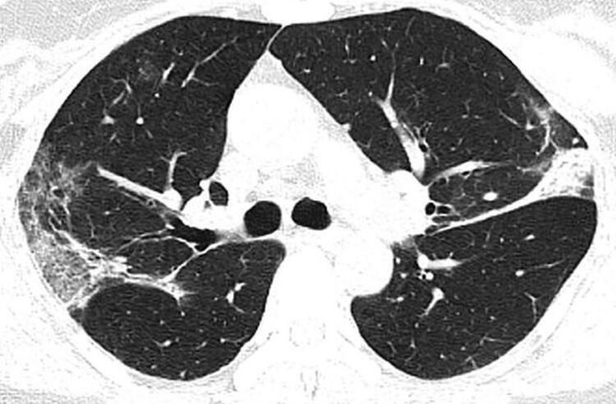

Röntgen görüntüleri ve bilgisayarlı tomografi taramaları, hastalığın kurbanlarının ciğerlerini nasıl tahrip ettiğini gözler önüne seriyor. Akciğerlerin alt köşelerindeki beyaz lekeler virüs varlığını gösteryor. Aynı lekeleri SARS ve MERS hastalıklarında da görmek mümkün.